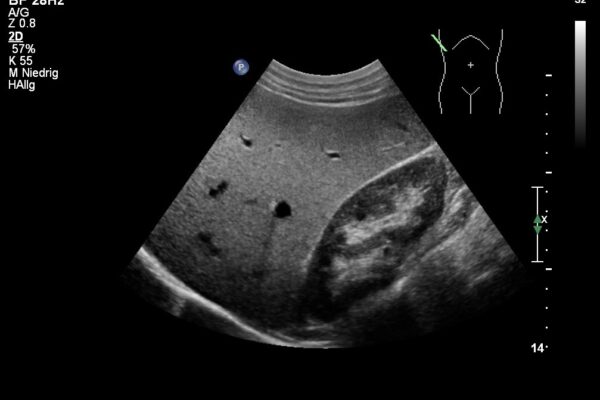

Die Bildgebung mittels Ultraschall (Sonographie) ist die am meisten genutzte, bildgebende Technik in der medizinischen Diagnostik. Dabei werden Schallwellen mit Frequenzen zwischen 1 und 40MHz benutzt. Die Ultraschallsonde (Schallkopf) sendet kurze Schallwellen aus, die im untersuchten Gewebe unterschiedlich stark reflektiert werden. Die reflektierten Schallsignale werden von der Ultraschallsonde wieder empfangen und vom Ultraschallgerät in Grauwerte auf dem Monitor dargestellt. So entsteht ein Ultraschallbild der inneren, von aussen nicht sichtbaren Organe und Strukturen. Dabei sind alle soliden oder blutreichen Organe (wie zB. Leber, Gallenblase, Nieren, Schilddrüse) und viele Gelenke (wie zB. Schulter, Knie, Hände und Füsse) gut untersuchbar.

Im Ultraschall der Bauchhöhle beurteilt der Arzt die Grösse, die Struktur und die Lage der Bauchorgane und Gefässe.